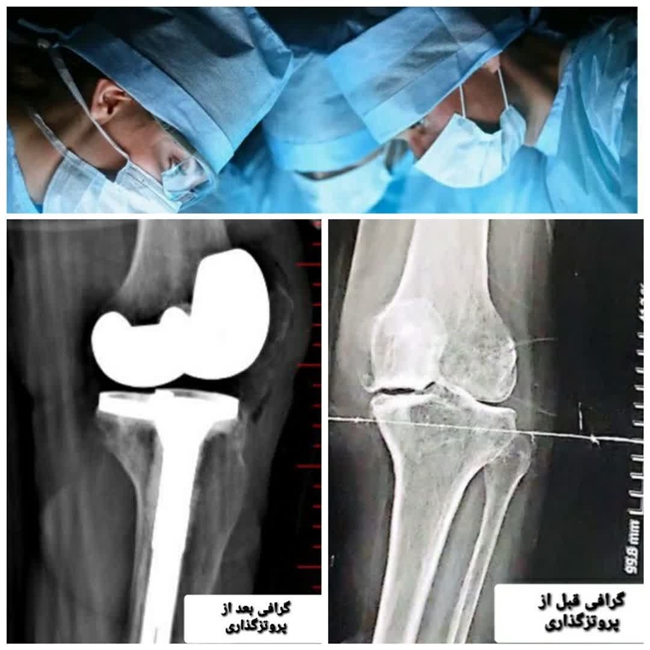

انجام عمل جراحی تعویض مفصل در بیمارستان جوین

رئیس بیمارستان قمربنی هاشم(ع)گفت:عمل جراحی پروتزگذاری (توتال آرتوروپلاستی)دیگری در بیمارستان جوین با موفقیت رقم خورد.

به گزارش وبدا/دکتر زهرا صباغ سجادیه در بیان این مطلب افزود:بیمار خانمی ۷۲ ساله مقیم شهرستان سبزوار که بر اثر کهولت سن و آرتروز شدید زانو رنج می کشید، با تعویض مفصل(پروتز گذاری) زانو در بیمارستان قمربنی هاشم (ع) درمان شد.

️ایشان خاطر نشان نمود: بیمار ابتدا با مراجعه به مراکز درمانی مشهد و عدم تقبّل پرداخت هزینه ی بالا از انجام پروتز گذاری منصرف و سپس با مراجعه به بیمارستان قمربنی هاشم (ع)این عمل جراحی با هزینه ی دولتی، توسط دکتر محمد داود رضایی پزشک متخصص ارتوپد با موفقیت انجام شد. ️

دکتر صباغ در پایان گفت: در بیمارستان قمربنی هاشم(ع) جوین علاوه بر عمل های جراحی ارتوپدی، تعویض مفصل زانو،شانه،هیپ،ران و... زیرنظر پزشکان متخصص ارتوپدی(دکتر محمد داود رضایی-دکتر سیدعلی اصغر سیّدی فرد) انجام میگردد.